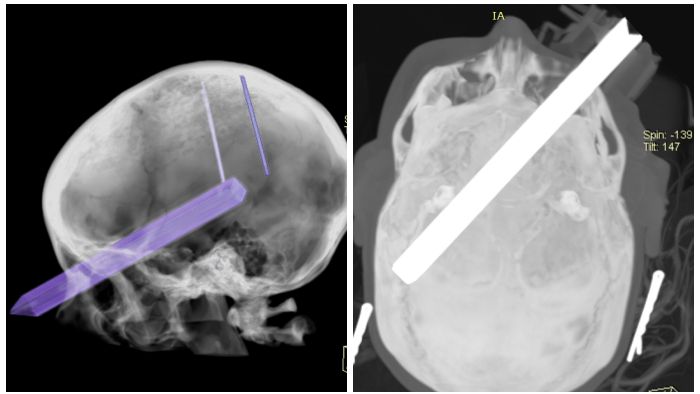

Wynik badania TK Zofii Zwolińskiej w dniu wypadku Wynik badania TK Zofii Zwolińskiej w dniu wypadku

Źródło zdjęć: © Archwium prywatne

Natychmiast wezwano pogotowie, które przetransportowało dziewczynę do szpitala. Wykonano badanie tomograficzne głowy, które uwidoczniło wymiar tragedii: metalowy trzonek od szczotki wbił się w oko, złamał kość oczodołu i umiejscowił na długości 19 cm w mózgu.

Wynik badania TK Zofii Zwolińskiej w dniu wypadku

Wynik badania TK Zofii Zwolińskiej w dniu wypadku © Archiwum prywatne